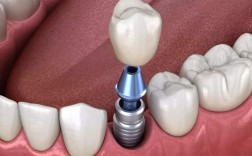

设备与材料支持

在硬件设备方面,杭州口腔医院配备了全套数字化种植系统,包括CBCT(锥形束CT)、3D口扫仪、数字化种植导板设计软件等,可实现术前精准模拟种植位置、角度及深度,减少手术创伤,提高种植体与骨组织的贴合度,材料选择上,医院提供多种国际主流种植体品牌,如瑞士Straumann(士卓曼)、瑞典Nobel Biocare(诺贝尔)、德国Ankylos(安格斯)、韩国Osstem(奥齿泰)、Dentium(登腾)等,覆盖不同预算和骨质需求的患者,种植体材质多为生物相容性良好的钛及钛合金,确保长期稳定性。